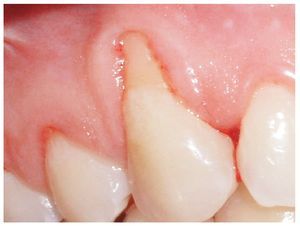

Dos mujeres de 36 y 25 años de edad fueron tratadas por recesiones gingivales en las caras vestibulares de los caninos superiores que les ocasionaban sensibilidad y problemas estéticos (figs. 1 y 2). Las pacientes presentaban buen estado de salud general y no presentaban ninguna contraindicación para la cirugía periodontal. No tenían alergias conocidas a ninguna medicación y negaron consumir alcohol. Tampoco eran fumadoras. Tras un exhaustivo examen clínico, recibieron instrucciones de control de placa y fueron sometidas a limpieza dental profesional en todas las superficies dentarias. Mediante una sonda periodontal manual graduada (CO 15 UNC, Hu-Friedy) se midieron la profundidad de la recesión, la encía queratinizada, profundidad de sondaje, y nivel de inserción clínica.

Figura 2. Aspecto inicial del caso 2.